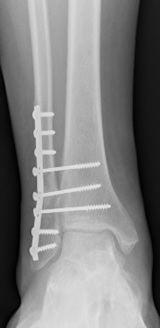

Seltener ist das Verbindungsband zwischen Schien- und Wadenbein im Sprunggelenksbereich betroffen. Im Rahmen von Überknöchelungstraumatas kann es zum Abreißen oder Einreißen dieser Bandstruktur führen. Damit verliert das Sprunggelenk seine Stabilität, da es schon beim Stehen zu einem vermehrten Aufklappen der Knöchelgabel kommen kann. Diese Verletzung tritt üblicherweise in Kombination mit anderen Verletzungen des Sprunggelenks, wie Knorpelschäden oder Rupturen der lateralen Sprunggelenksbänder auf.

Bei frischen Verletzungen können meistens Bandanteile mit Fäden augmentiert und am Knochen wieder fixiert werden. Mitunter erfolgt die Fixierung des Bandes mittels im Knochen eingebrachter Ankersysteme, über die das Band angenäht werden kann. Um ein Ausreißen der Anker bzw Fäden verhindern zu können, werden üblicherweise „Stellschrauben", die das Wadenbein am Schienbein etwas oberhalb des Sprunggelenks fixieren, gesetzt.

Diese Schrauben müssen vor Beginn der Gehbelastung in aller Regel entfernt wieder werden. Alternativ kann ein sogenanntes Tight Rope, ein Kunstband, das über einen Bohrkanal das Schien- am Wadenbein fixiert, verwendet werden.